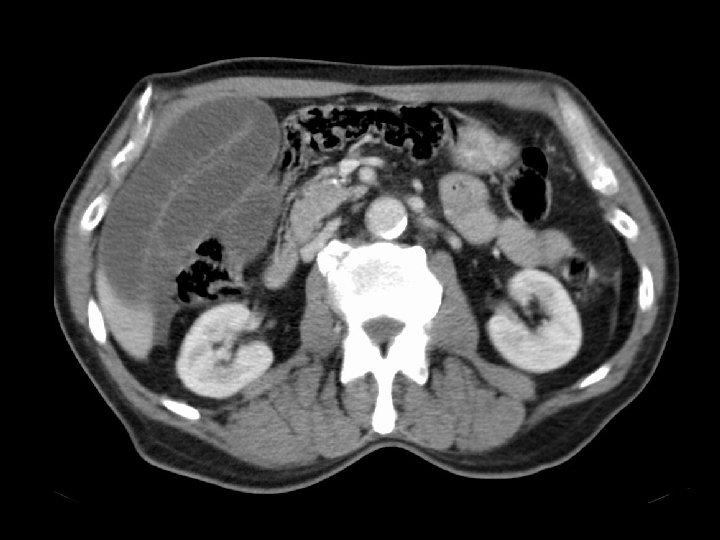

Von-Hippel Lindau • Findings: – Numerous bilateral renal cyst – Solid enhancing right renal mass = RCC • ddx: – NONE! – This is an Aunt Minnie!